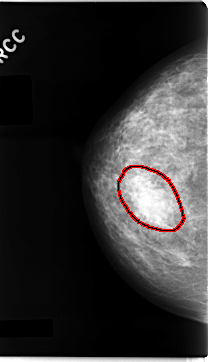

ics_version 1.0 filename C-0060-1 DATE_OF_STUDY 11 3 1993 PATIENT_AGE 47 FILM FILM_TYPE REGULAR DENSITY 3 DATE_DIGITIZED 23 10 1997 DIGITIZER LUMISYS LASER SEQUENCE LEFT_CC LINES 4704 PIXELS_PER_LINE 2624 BITS_PER_PIXEL 12 RESOLUTION 50 OVERLAY LEFT_MLO LINES 4704 PIXELS_PER_LINE 2512 BITS_PER_PIXEL 12 RESOLUTION 50 OVERLAY RIGHT_CC LINES 4704 PIXELS_PER_LINE 2696 BITS_PER_PIXEL 12 RESOLUTION 50 OVERLAY RIGHT_MLO LINES 4712 PIXELS_PER_LINE 2672 BITS_PER_PIXEL 12 RESOLUTION 50 OVERLAY |

FILE: C_0060_1.RIGHT_CC.OVERLAY TOTAL_ABNORMALITIES 1 ABNORMALITY 1 LESION_TYPE MASS SHAPE OVAL MARGINS CIRCUMSCRIBED ASSESSMENT 3 SUBTLETY 5 PATHOLOGY BENIGN TOTAL_OUTLINES 1 BOUNDARY |